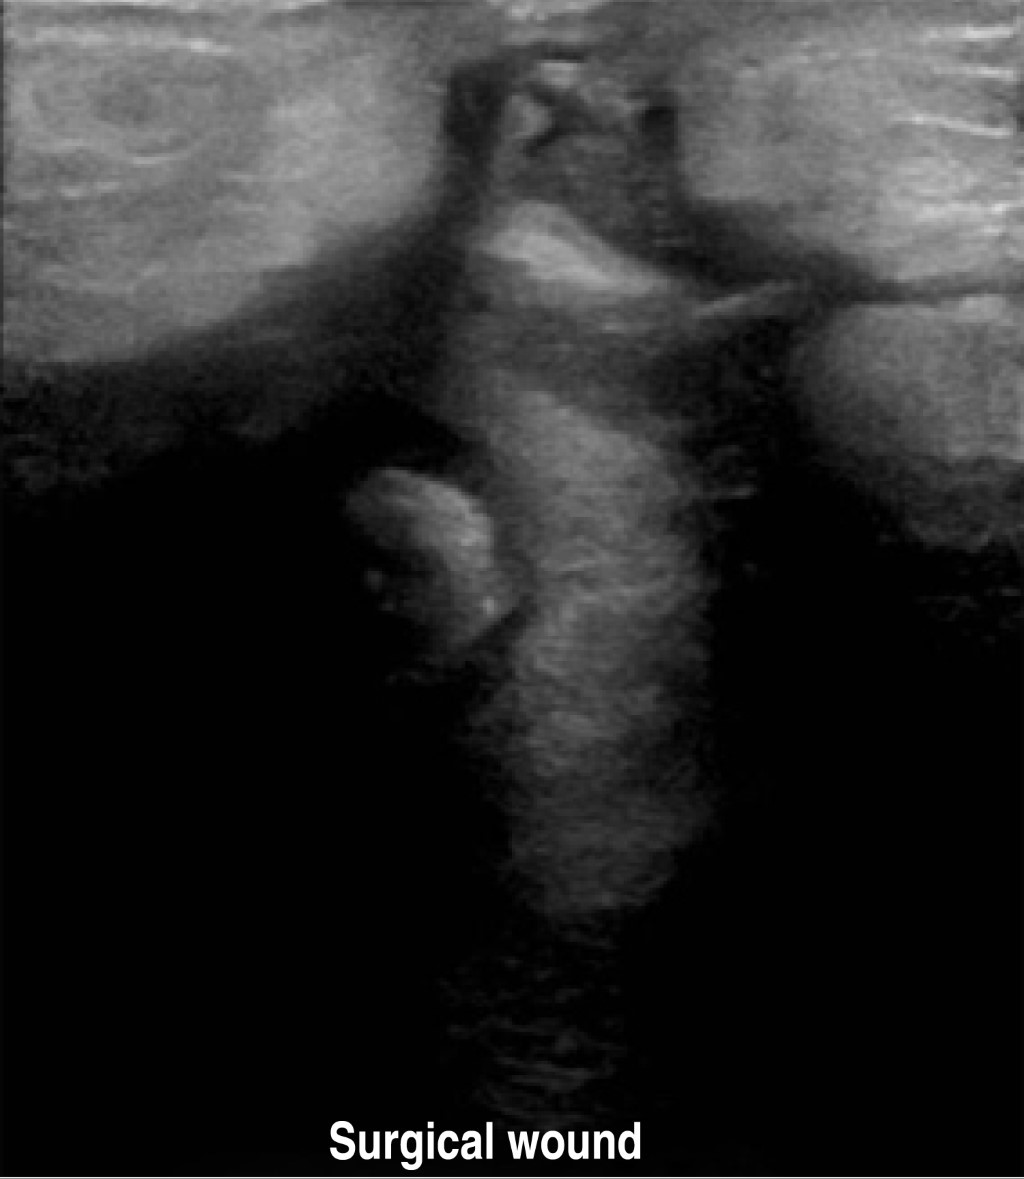

A 40-year-old female patient had four gestations, three deliveries, and a history of aortic valve stenosis since 2017 with surgical management based on valve prosthesis placement and use of acenocoumarin until the diagnosis of her last pregnancy, during which oral the anticoagulant drug was suspended, and enoxaparin was started. She started her current condition when she was admitted to the obstetrics service with a gestational age report of 28.5 weeks of gestation (SDG) by the last menstrual period and 29.4 by fetometry. Preeclampsia was diagnosed with severe data, so it was decided to perform a Kerr cesarean section and bilateral tubal occlusion with Kroener technique, reporting 350 cm3 of bleeding, obtaining a single live male product of 31.5 weeks by Capurro, with an Apgar score of 7/8, and with cleft lip and palate. She was discharged on the fifth day, requiring a transfusion of blood products in her immediate postoperative period. Twenty-one days later, she was readmitted due to abundant and fetid bleeding through the surgical approach; wound healing was performed, and an abdominal wall defect was evidenced, so it was decided to perform an ultrasound, with findings of a defect in the anterior abdominal wall in the cephalic portion of the wound through which intestinal loops protrude (Figures 1 and 2). In an abdominal computerized tomography scan, a heterogeneous non-measurable collection was identified in the middle and caudal third of the wound at the level of the subcutaneous plane, as well as a thick-walled collection in the pelvic cavity and left iliac fossa (Figure 3).

Figure 1